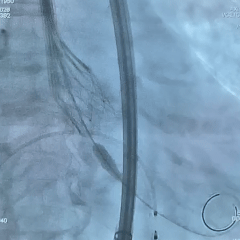

术中影像

双窦展开位根部造影

瓣叶狭窄明显,无明显反流

直头导丝顺利跨瓣

猪尾导管测量跨瓣压差约70mmHg

18mm球囊预扩,球囊上下滑动,无腰无漏,左冠显影,右冠无显影

输送系统顺利过弓

造影确认初始定位零位

瓣膜稳定展开

全展开位造影评估

瓣架呈直筒型,位置接近0位,少量反流

瓣膜缓慢脱钩,可见瓣膜实现自同轴,且无位移

脱钩后造影评估

瓣架形态佳位置可,冠脉显影,导丝压瓣可见反流

最终根部造影

撤出心室导丝后,反流明显减少